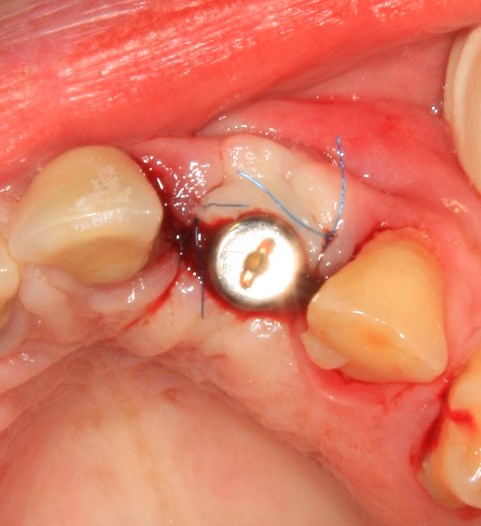

И швы:

Как и на первом этапе, мы делаем назначения и даем рекомендации, а также в течение нескольких дней контролируем состояние послеоперационной раны.

Вот так она выглядит через день после операции:

Разумеется, пациентку никто не оставляет без зуба. Если Вы обратили внимание, то заметили справа на правой фотографии остатки металлического ретейнера. С помощью него к соседним от дефекта зубам фиксируется адгезивная коронка. Она, конечно же, не дает возможности нормально кусаться, но зато отлично маскирует отсутствие зуба. Таким своеобразным временным протезированием пациентка пользуется от начала и до конца лечения.